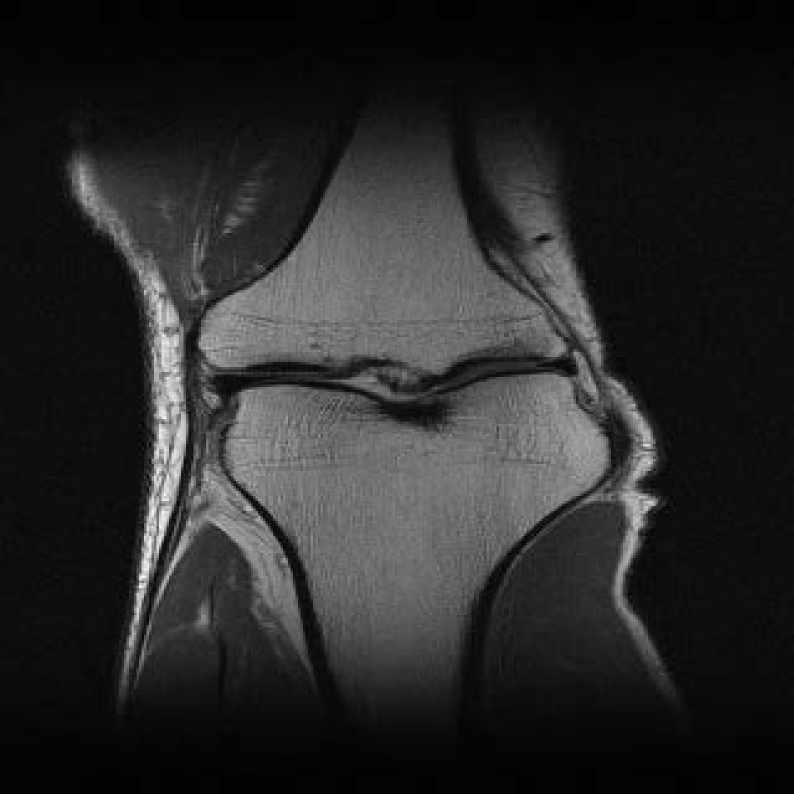

4.2.3 Accelerated Multi-coil MRI

In this subsection, we report the comparative performance of EI, SkEI and C-SkEI in multicoil MRI reconstruction task. We evaluate the performance of two distinct Sketched-EI methods proposed in this study for multicoil MRI, using a knee MRI image with 15 coils from zbontar2018fastmri . Subsequently, we performed a comparative analysis of the reconstruction results under two distinct sketch schemes and varying sketch sizes. Consistent with Section 4.2.1, we begin by comparing our proposed methods with the vanilla DIP method, considering the same DIP network architectures as outlined in Section 4.2.1.

For SkEI and C-SkEI schemes, SS is defined as the sketch operation that samples N15N\leq 15 coils from the original 15 coils, then forms a minibatch named ASNA_{S_{N}}. However, these two sketch schemes differ in their minibatch partition strategies. Specifically, as described in Algorithm 3, Coil-Sketch compresses the initial 15 coils and then selects the first LL compressed virtual coils as the new multi-coils. Subsequently, the first RR higher-energy virtual coils are retained, while the last SS lower-energy virtual coils undergo sketch operation. In contrast, Classical-Sketch directly acts on the original 15 coils, randomly sampling the NN coils into a minibatch. During each iteration, the minibatch is randomly chosen from the 15 coils for updates. For this study, we experiment with N=10,5N=10,5 and 22, respectively.

The visualized comparisons are shown in Figure 9, as can be seen, the performance of the DIP method is still suboptimal, consistent with findings from the sparse view CT experiments. In comparison, the EI method achieves remarkable improvements in reconstruction quality due to the EI regularizer. Furthermore, the reconstruction results generated by these two proposed sketch methods exhibit almost no loss in performance and even surpass the vanilla EI method. Furthermore, as presented in Figure 11 (b), the time cost per iteration of the sketched EI decreased compared to the vanilla EI method. Specifically, C-SkEI-2coils decreased 19% per iteration compared to vanilla EI, while SkEI-2coils (with subsampling sketches) decreased 17%. Moreover, we observe that C-SkEI demonstrates a much faster convergence rate compared to that of standard EI.

To further explore our schemes, we performed ablation studies with three different sketch sizes in two different sketch methods, as visualized in Figure 10 and Figure 11(a). The results show that for C-SkEI, performance improves significantly when the sketch size increases to 5 but decreases slightly when the size reaches 2. Nevertheless, all three sketch sizes outperform the vanilla EI, attributed to the sketch algorithm optimized for multicoil MRI. In contrast, for plain SkEI with the classical subsampling sketch, performance initially increases with smaller sketch sizes, but significantly deteriorates once the size reaches 2, performing much worse than vanilla EI. Furthermore, as presented in Figure 11(a), compared to the vanilla EI method, both SkEI methods converge faster in the first 300 seconds of training. In particular, the C-SkEI method converges even faster than plain SkEI while maintaining performance levels that far exceed vanilla EI. Both schemes reach their own fastest convergence when the sketched size is 10.

Refer to caption

xx (GT)

C-SkEI-10coils

C-SkEI-5coils

C-SkEI-2coils

*EI-full (15coils)

SkEI-10coils

SkEI-5coils

SkEI-2coils

Figure 10: Multi-coil MRI Images (with corresponding PSNR) reconstructed by Sketched EI, with different sketch sizes, and ‘SkEI-’ shorts for SkEI with subsampling sketch, ‘C-SkEI-’ stands for C-SkEI with coil-sketch. ‘*’ denotes the baseline.

(a): MSE variation with time up to 300 seconds of the proposed EI with different sketched size for both classical sketch and coil sketch schemes.

Method Time (s) / Epoch

*EI-full 0.157

C-SkEI-10 0.151

C-SkEI-5 0.134

C-SkEI-2 0.130

SkEI-10 0.141

SkEI-5 0.129

SkEI-2 0.127

(b): Time cost per iteration of the proposed SkEI / C-SkEI with different sketched size for both classical sketch and coil sketch schemes.

Figure 11: MSE and time cost comparisions of the proposed sketched EI and vanilla EI method in 15 coils knee MRI reconstruction.‘SkEI-’ shorts for SkEI with subsampling sketch, ‘C-SkEI-’ stands for C-SkEI with coil-sketch. ‘*’ denotes the baseline.